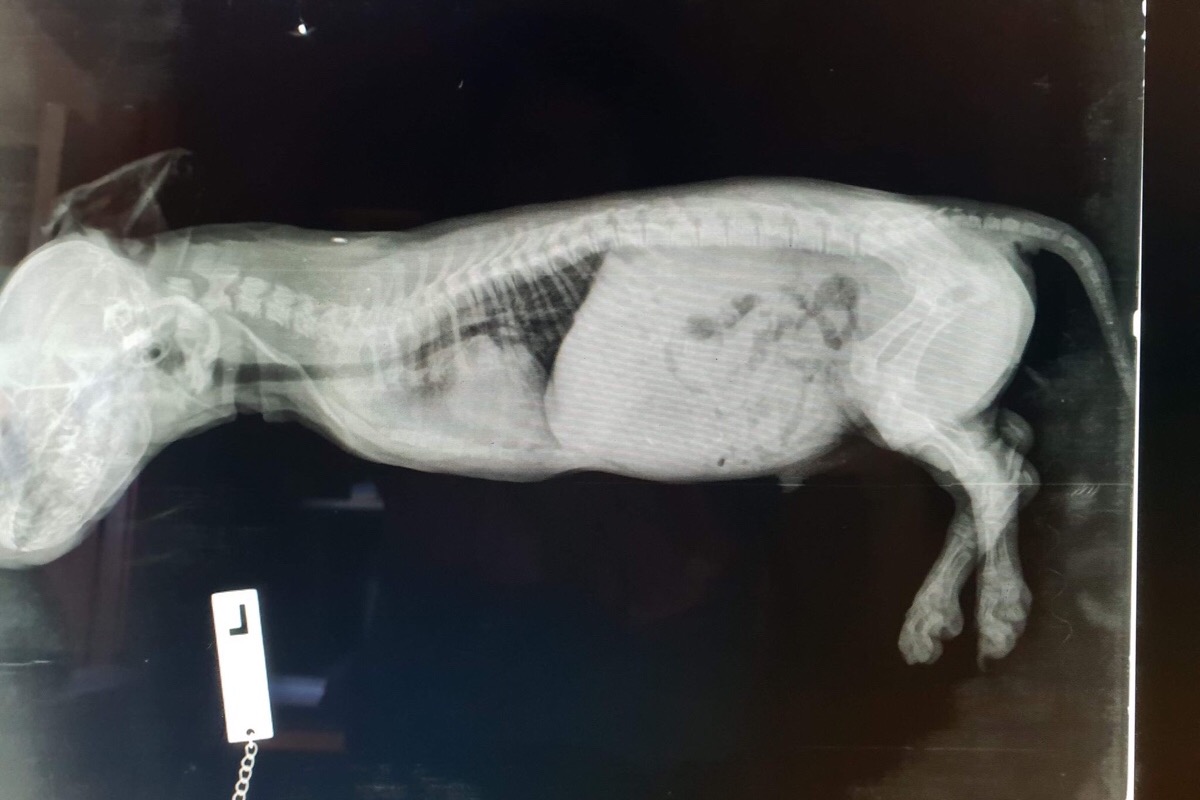

Baby Forest is a 12 week old Miniature Dachshund puppy that was born without front legs. He has a huge spirit and such an infectious personality. Nothing can stop him, his determine and courage is just amazing. Forest is a Special Needs Puppy and requires lots of care and attention. With this fundraiser we hope to get him a few sets of wheels that will help him as he grows and get him a bit more mobile.

(Fast asleep waiting for his X-ray)